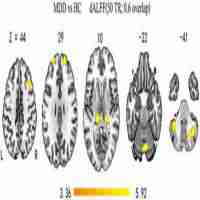

| Abstract | Antidepressant medications represent the most common treatment option for major depressive disorder (MDD), but the neuro-psychological mechanisms by which antidepressants act to improve depressive symptoms remain under-specified. We designed this study to assess the effects of escitalopram treatment on spontaneous brain activity of MDD patients using functional magnetic resonance imaging (fMRI). Twenty first-episode drug-naive MDD patients received resting-state fMRI scans before and after 8 weeks of treatment with a selective serotonin reuptake inhibitor - escitalopram. Twenty age- and gender-matched healthy controls were also scanned twice with an 8-week interval. The fractional amplitude of low-frequency fluctuation (fALFF) was used to characterize the spontaneous brain activity. The analysis of covariance (ANCOVA) was performed to determine treatment-related changes in fALFF. The symptoms were significantly improved in MDD patients after treatment. We observed significant group-by-time interaction on fALFF in the left dorsomedial prefrontal cortex, the right middle frontal gyrus, and the left putamen. Post-hoc analyses showed that the fALFF values in these regions were significantly higher in the MDD patients compared to healthy controls at baseline and were reduced after treatment. The findings suggest that abnormalities in the brain areas involved in emotional processing and regulation could be normalized by effective antidepressant treatment with escitalopram in the MDD patients and free of a task situation. |